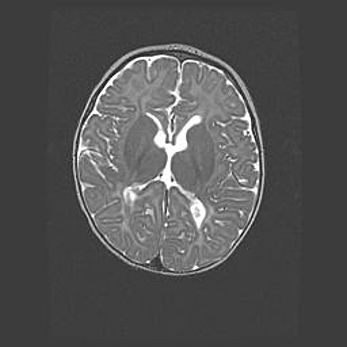

Наружная гидроцефалия с возможной атрофией височных областей.

Возраст: 28 дней

Вес: 3670 г

Пол: мужской

Окружность головы: 38 см

Срок гестации: 40 недель

Гидроцефалия головного мозга у новорожденных – это заболевание, которое характеризуется скоплением избыточного количества спинномозговой жидкости в желудочковой системе головного мозга в результате затруднения её перемещения от места выработки к месту поглощения в кровеносную систему или вследствие нарушения абсорбции. При открытой наружной форме гидроцефалии у новорожденных расширяются и переполняются субарахноидные пространства.

При нормотензивных  формах,  которые,  как  правило,  являются  следствием  перенесенных ишемических  повреждений  паренхимы  мозга,  возможно  сочетание микроцефалии  с нормотензивной гидроцефалией. В основе данных изменений лежит атрофия больших полушарий с преимущественной  локализацией  в  лобно-височных  областях.